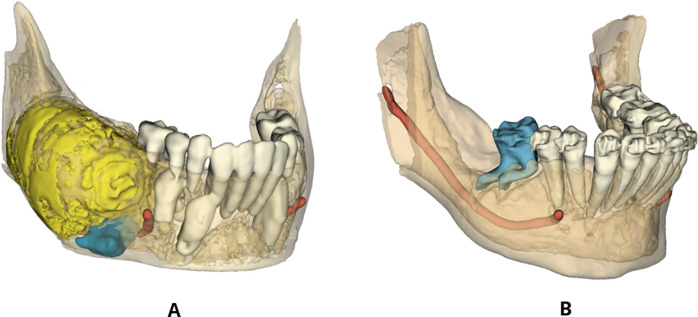

Methods: The sample size consisted of 22 impacted teeth divided into two groups: with odontogenic lesions (Group IwL) and without lesions (Group IwoL). Pre- and post-treatment radiographs, taken before and after conservative surgical or orthodontic-surgical management of impacted teeth, were used to assess the occurrence of dilaceration in both groups. Fisher's exact text was applied to compare the prevalence of dilaceration in both groups. In order to analyze the influence of each additional variable on dilaceration, a multivariate analysis was performed through logistic regression.

Results: Root dilaceration was significantly more common in Group IwL (72.73%) than in Group IwoL (18.18%) (p = 0.030). No significant association was found between root dilaceration and additional variables, including impaction depth, cortical bone contact, maximum lesion size, and lesion volume.

Conclusions: This study provides novel evidence for a correlation between odontogenic lesions and root dilaceration, suggesting that compressive forces from these lesions may significantly contribute to abnormal root development, with important implications for clinical diagnosis and treatment planning.